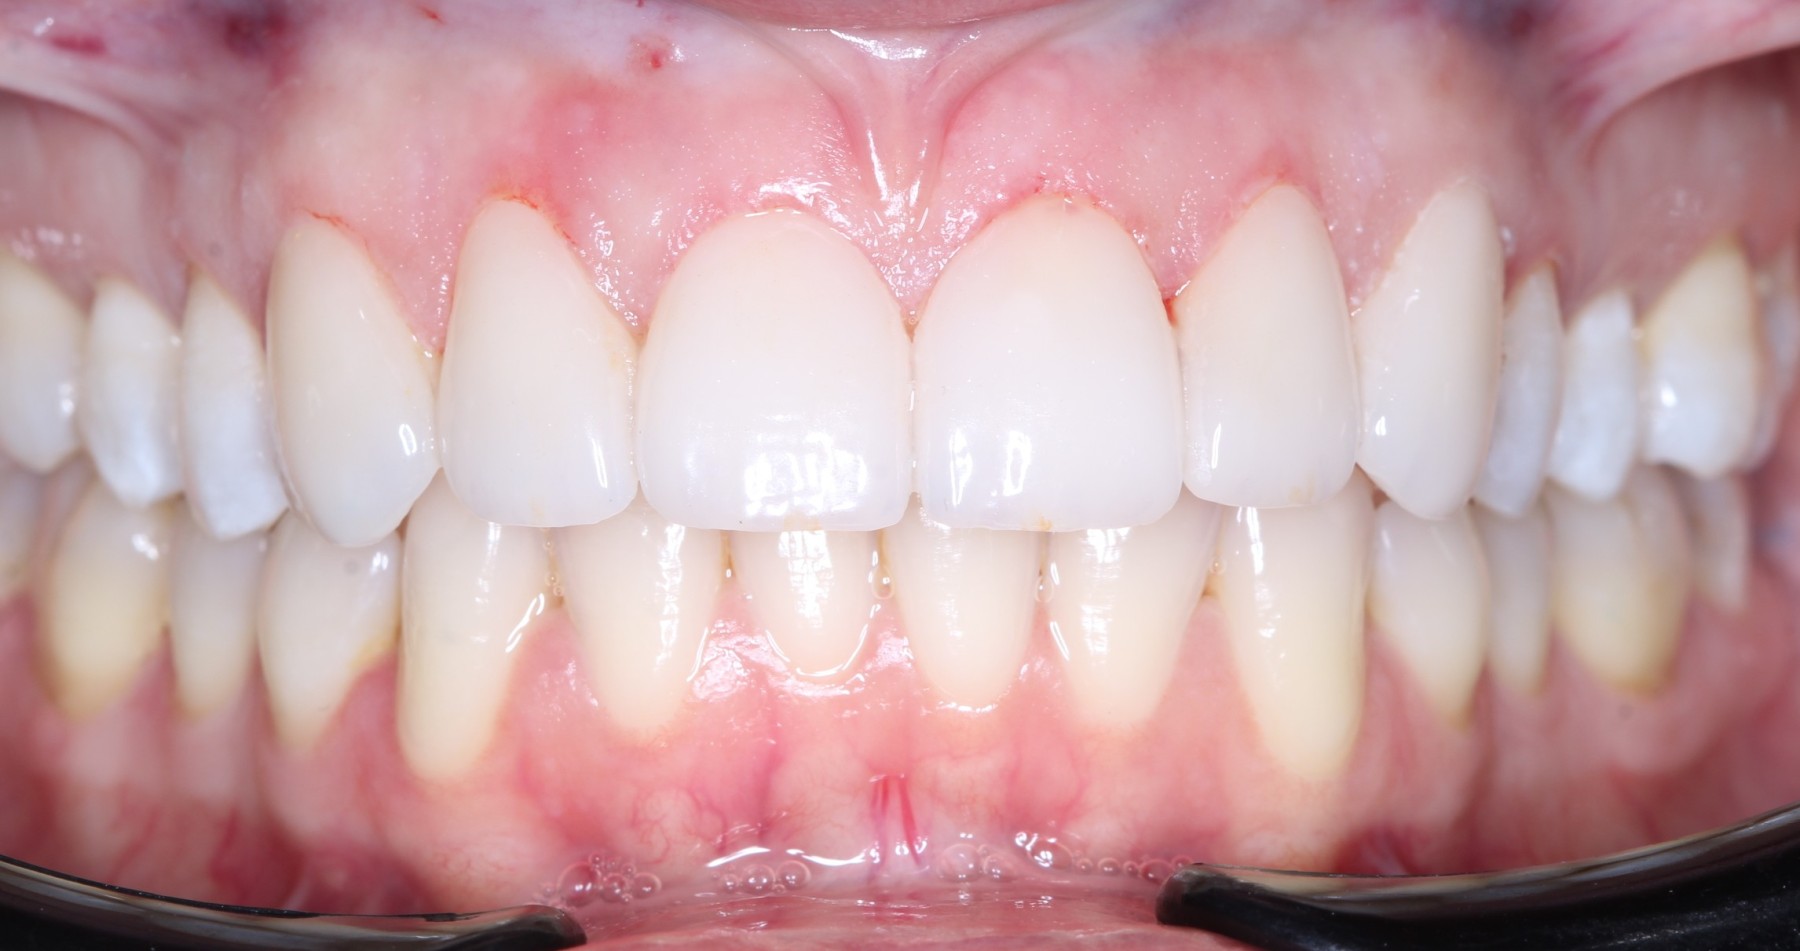

Se realizan 6 carillas dentales en Emax, mejorando frente estético, y funcion masticatoria.